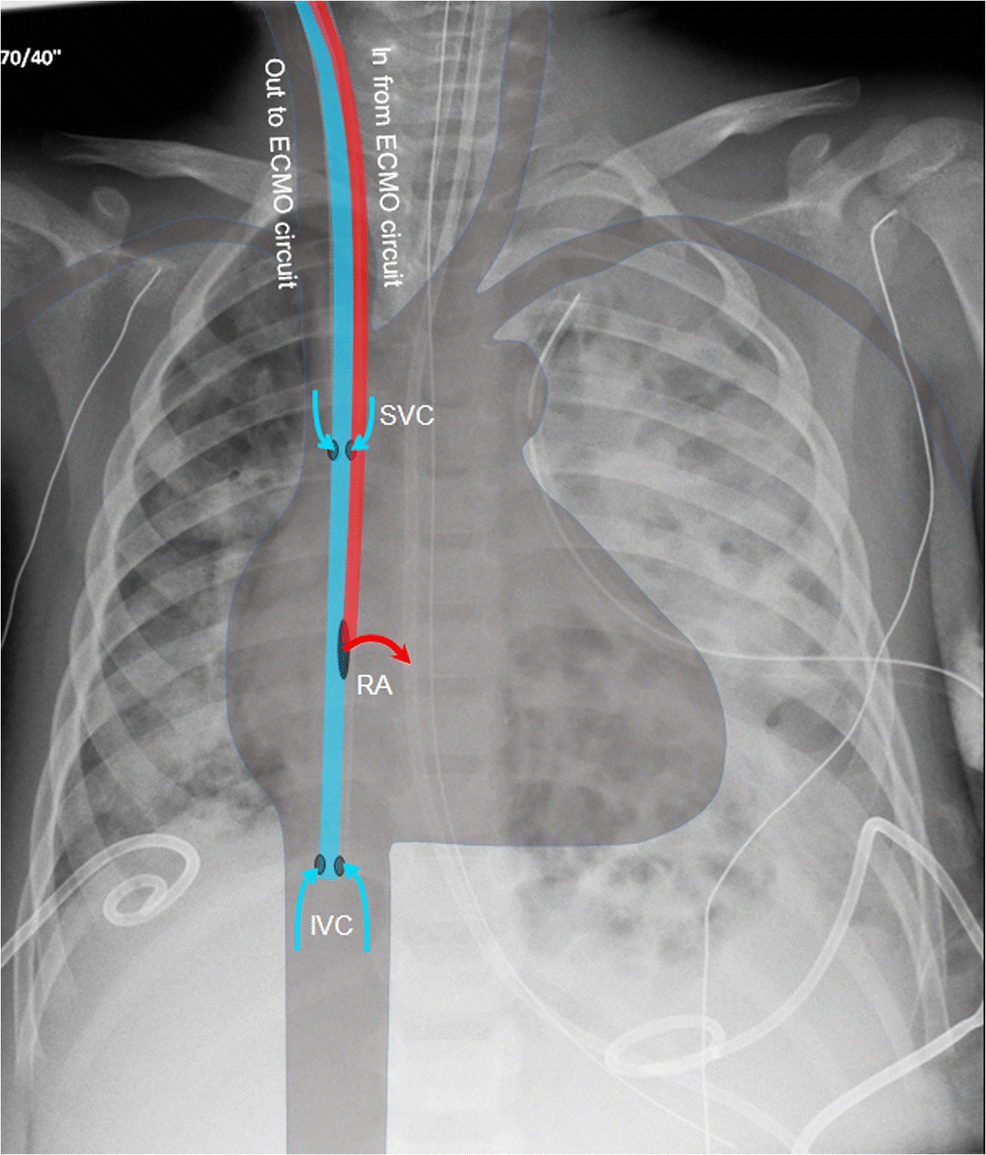

Everything ECMO Cannula and Cardiac Curveballs INTENSIVE Ecmo Catheter X Ray a surgeon, assisted by an operating room team, inserts the ecmo catheters into either an artery or veins. key points • femoroatrial vv ecmo: extracorporeal membrane oxygenation (ecmo) is increasingly widely used in pediatric respiratory failure. Despite playing a key part in patient management. Femoral vein drainage cannula and right atrial return cannula. the purpose of. Ecmo Catheter X Ray.

What to do when the SpO2 still stays low on VVECMO? INTENSIVE Ecmo Catheter X Ray key points • femoroatrial vv ecmo: Tee has been used to guide placement of venovenous ecmo cannulation. extracorporeal membrane oxygenation (ecmo) is increasingly widely used in pediatric respiratory failure. the purpose of this review is to familiarise radiologists with the imaging features of ecmo devices, their associated. a surgeon, assisted by an operating room team, inserts. Ecmo Catheter X Ray.